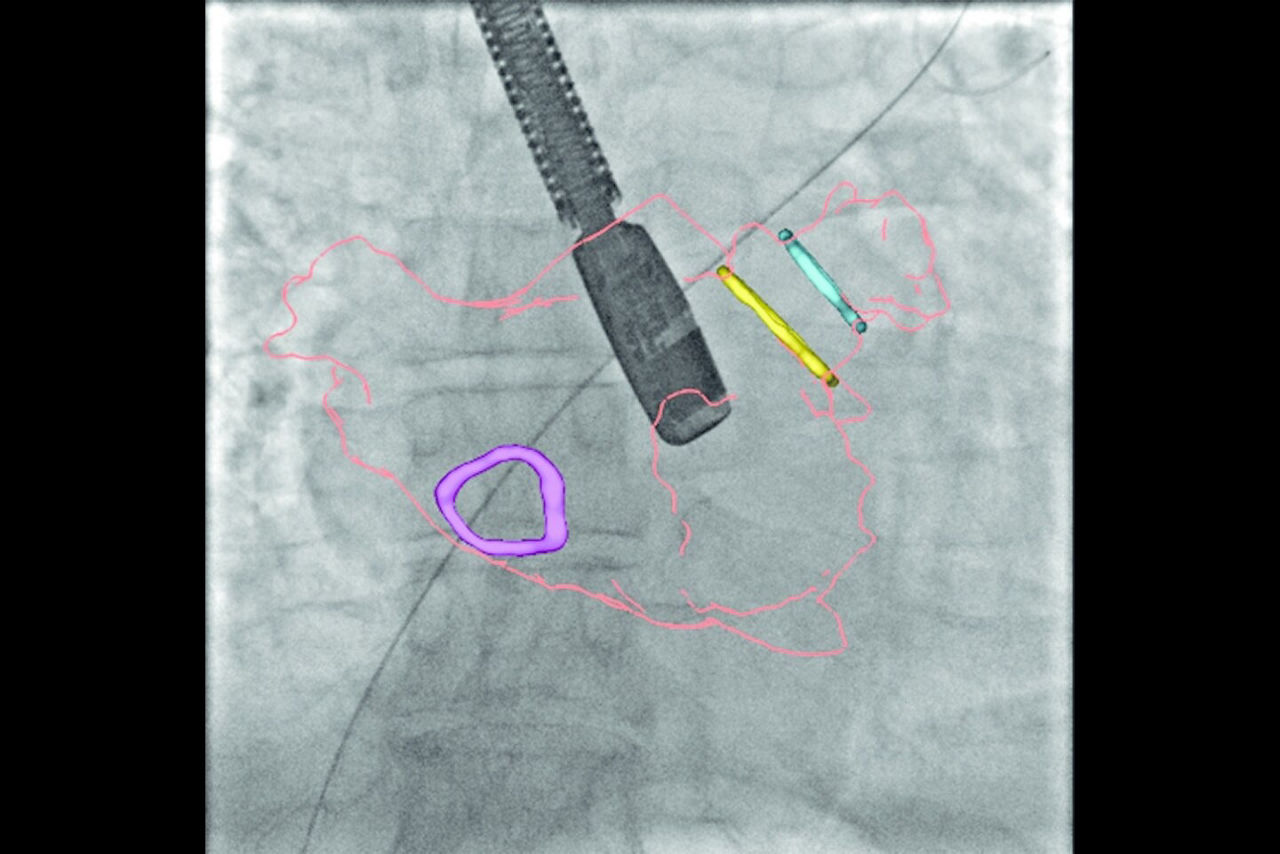

Left atrial appendage closure

Augmented guidance for more confidence with LAAC

GUIDE

3D fusion helps guide each step with confidence, from the trans-septal puncture to the device deployment. Significantly reduce procedure time, while decreasing contrast media and dose.

ASSESS

Once the device is deployed, employ echocardiography to confirm the device location and evaluate compression before releasing the device⁴.

With Valve ASSIST 2, improve your patient outcomes in LAAC⁵:

• 78% reduction in volume of contrast media

• 28% reduction in procedure time

• 25% reduction in fluoroscopy time